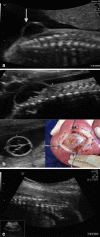

The advance in the imaging tools during the pregnancy (ultrasound and magnetic resonance) allowed the early diagnose of many fetal diseases, including the neurological conditions. This progress brought the neurosurgeons the possibility to propose treatments even before birth. Myelomeningocele is the most recognized disease that can be treated during pregnancy with a high rate of success. Additionally, this field can be extended to other conditions such as hydrocephalus and encephaloceles. However, each one of these diseases has nuances in the diagnostic evaluation that should fit the requirements to perform the fetal procedure and overbalance the benefits to the patients. In this article, the authors aim to review the neurosurgical aspects of the antenatal management of neurosurgical conditions based on the experience of a pediatric neurosurgery center.